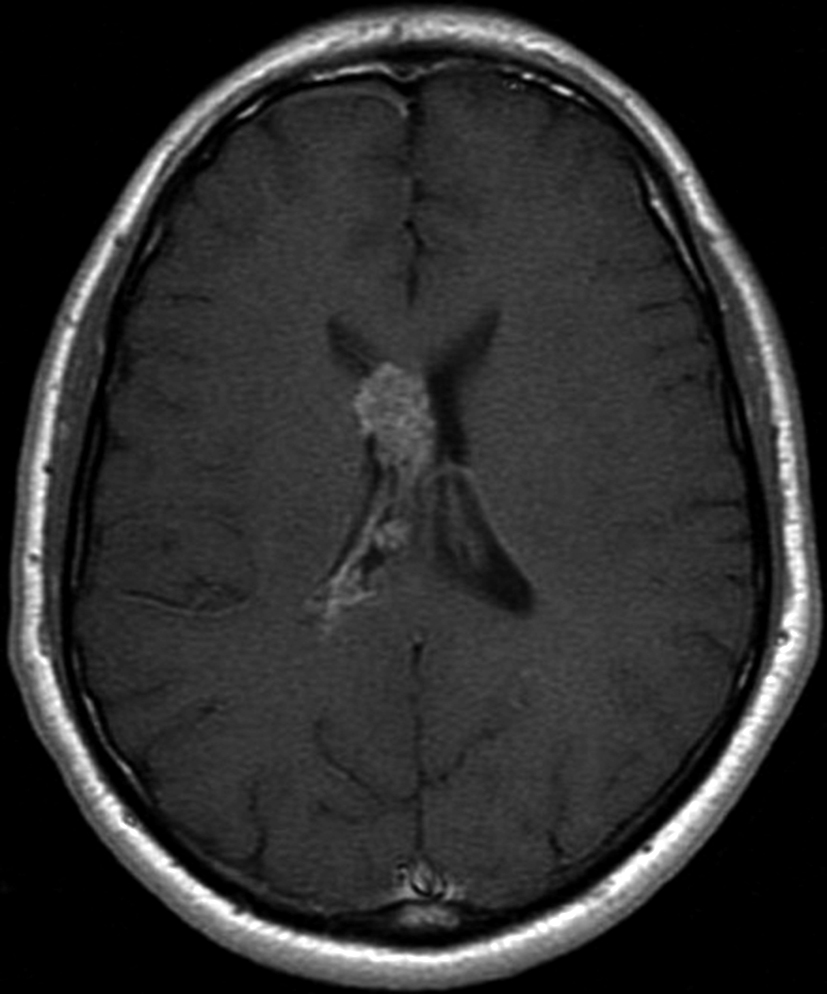

Con los hallazgos tomográficos, no se efectúan planteos diagnósticos y se realiza una resonancia magnética con la finalidad de obtener más datos semiológicos en busca de una aproximación diagnóstica. Se realizó el estudio por medio de secuencias T 1, FSE T 2, FLAIR, SWI y Difusión, en cortes axiales, FSE coronal y sagital T 1. Se realiza la administración de gadolinio DTPA en los tres planos. Se evidencia la lesión bien definida a nivel del ventrículo lateral derecho, que involucra al tronco del cuerpo calloso (Figura 2- C y 3- B). Presenta intensidad de señal heterogénea en secuencias T1 y T2 (Figura 3 y Figura 4). En secuencia ecogradiente se observa una señal marcadamente hipointensa y heterogénea, con un halo hipointenso bien definido (Figura 2- C). No presenta realce significativo tras la administración de Gadolinio (Figura 2- B) y en la secuencia de difusión no presenta restricción.

Figura 2 Resonancia magnética.

a) Imagen axial T1, lesión intraventricular con intensidad de señal heterogénea.

b) Tras la administración de Gadolinio no presenta realce significativo.

c) Imagen axial en secuencia ecogradiente donde se evidencia la lesión

hipointensa y heterogénea. Se observa la extensión de la lesión al cuerpo calloso.